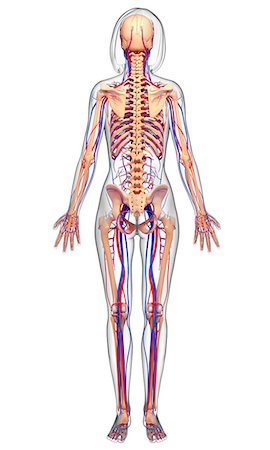

Femoral Artery And Pelvic Bones Stock Photos Page 1

Femoral Artery And Pelvic Bones Stock Photos Page 1